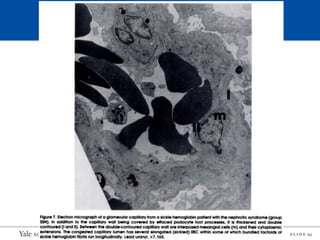

Pathology

Main glomerular pathologies associated with SCD:

1. Glomerular hypertrophy without overt sclerosis

2. Focal segmental glomerulosclerosis (FSGS) and its variants (e.g

collapsing FSGS)

3. Membranoproliferative glomerulonephritis (MPGN)

4. Thrombotic microangiopathy (TMA)

FSGS